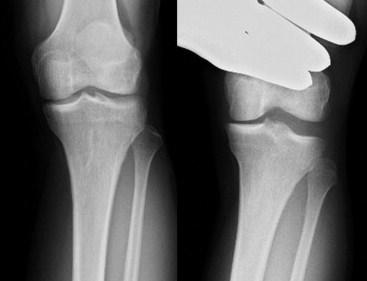

초기에는 보조기나 약물 치료, 점진적인 재활 등으로 대증적 치료를 시도해보며,

1cm 이상의 joint opening 이 보일 경우 LCL ligament repair, reconstruction (with/without PLC) 등을 시도해 볼 수 있습니다.